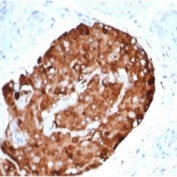

IHC staining of FFPE human testicular carcinoma with recombinant INHA antibody (clone rINHA/6919) at 2ug/ml in PBS for 30min RT. HIER: boil tissue sections in pH 9 10mM Tris with 1mM EDTA for 20 min and allow to cool before testing.